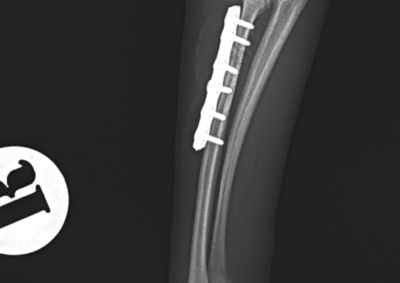

整形外科 注意 ボタンをクリックした先に、治療中および手術中の画像が説明で使用されている場合がございます。 そのような画像に弱い方は閲覧なさらないようお願いいたします。 整形外科 股関節脱臼に対するBUSTOR #65 整形外科 若齢犬の脛骨骨折 整形外科 橈尺骨固定術 #259 整形外科 膝蓋骨内方脱臼 G4 整形外科 膝蓋骨内方脱臼 G2~3 整形外科 橈骨固定術 #258 整形外科 膝蓋骨内方脱臼G3 整形外科 MPL G2 整形外科 CBLO #241 整形外科 膝蓋骨内方脱臼G3 整形外科 LCPDに対するFHNE 整形外科 CBLO#240 × Piezosurgery <12345678> 症例カテゴリー 放射線治療整形外科軟部組織外科脳神経外科内科腫瘍外科救急・集中治療リハビリテーション科腫瘍内科内視鏡科脳神経科呼吸器外科中医・漢方猫の腎移植循環器科